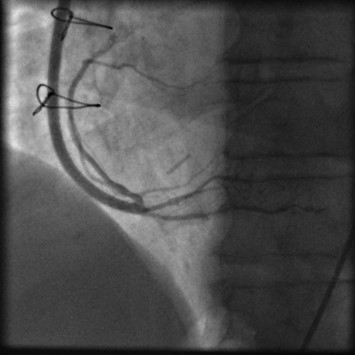

Follow-up of patient with open XABG Conduit